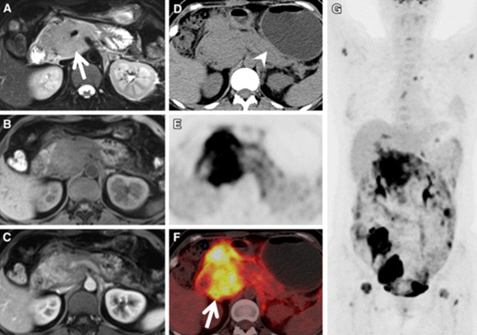

患者,女性,46岁,间歇性上腹部疼痛9个月。常规PET/CT平扫CT显示胰头低密度灶(A),FDG摄取增高(B、C,SUVmax = 2.93),根据代谢特点怀疑胰头癌;增强CT胰腺实质期(D)见胰头区低强化灶,门脉期病灶强化程度明显增加,密度接近周围正常胰腺组织(E),PET图像与门脉期增强CT图像融合,同时显示病灶的FDG摄取及增强特点(F)。本例PET/CT与增强CT融合图像特征,诊断胰腺炎,后经随访证实,而常规PET/CT很容易误诊为胰腺癌。